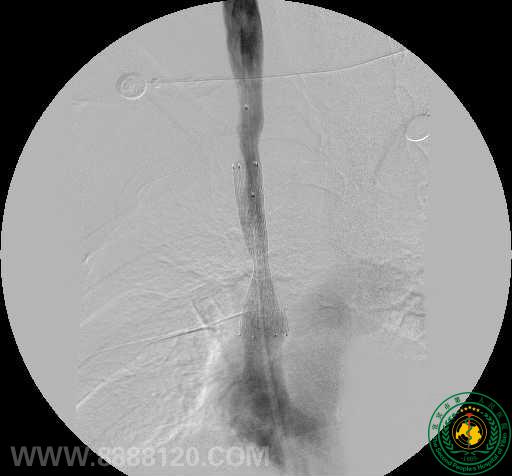

影像科介入组近日完成一例上腔静脉支架植入术

影像科介入组近日完成一例上腔静脉支架植入术3067